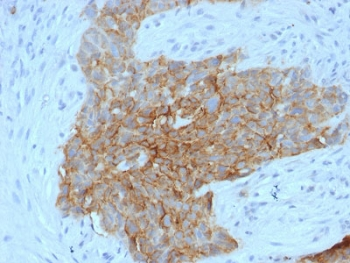

IHC staining of FFPE human ovarian carcinoma tissue with SLC2A1 antibody (clone GLUT1/7308). Inset: PBS used in place of primary Ab (secondary Ab negative control). HIER: boil tissue sections in pH9 10 mM Tris with 1 mM EDTA for 20 min and allow to cool before testing.